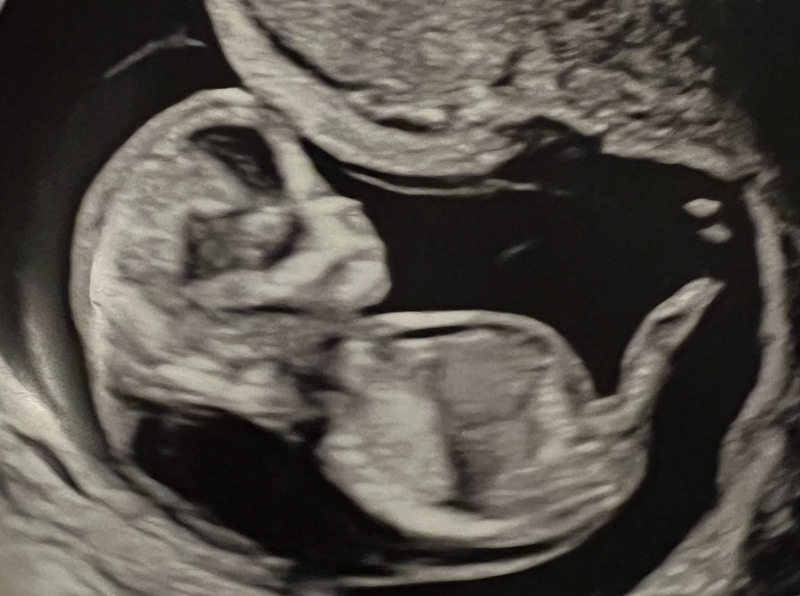

On April 21, Adkins saw her doctor for a routine screening by ultrasound to measure the collection of fluid behind the fetus’ neck. And even without a medical degree, she could tell by the picture on the ultrasound that something was wrong. Sitting in the genetic counselor’s office that afternoon, Adkins learned her 12-week-old developing fetus likely had Turner syndrome, a chromosomal abnormality that ends in miscarriage in 99% of cases.

The normal measurement is less than 3 millimeters, according to Dr. Maria Palmquist, a maternal-fetal medicine specialist at Saint Alphonsus Regional Medical Center in Boise, Idaho. Palmquist said Adkins’ fluid measured at 11.7 millimeters, with additional fluid accumulating under the skin and around the body of the fetus, known as edema. The combination of increased fluid and skin edema is a condition known as hydrops fetalis, a severe form of swelling that is often fatal.

She hoped to miscarry within the following week so they wouldn’t have to make the emotional three-day trip. So she scheduled another ultrasound, but there was still a heartbeat. She was desperate to fix it — desperate to stop being a walking coffin for a dying dream.